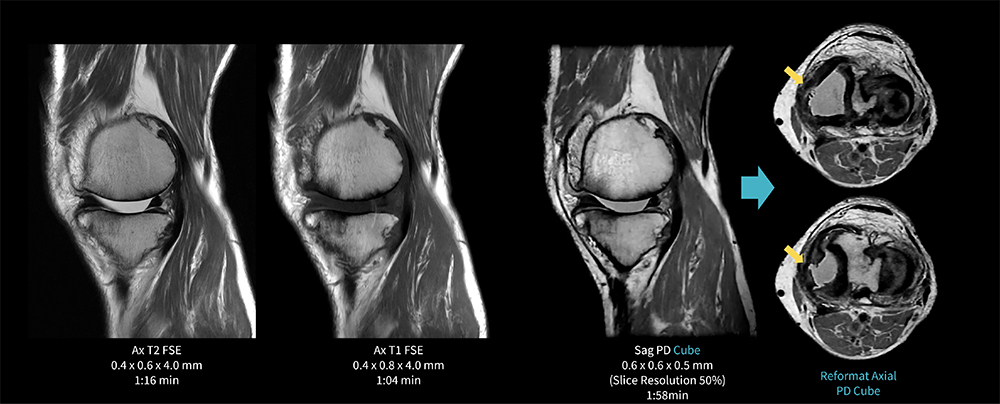

Case9 Cube/変形性膝関節症+内側半月板損傷

80代、男性。変形性膝関節症にてMRI検査を施行した。

膝関節内側の軟骨は著明に菲薄化。内側半月板は大きく関節外方向へ偏位しており、中節に断裂を認める。

AIR Recon DLを併用した3D PD Cubeは短時間撮像でもMPRで観察可能である。

MR30_Kariyatoyota_11.jpg図9 Cubeを用いた膝関節検査